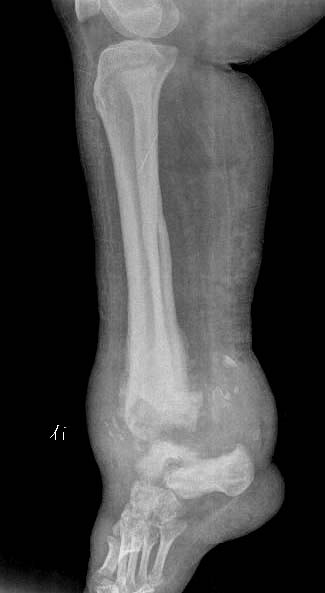

女.29岁.先天髋关节脱位.腰椎后部向外膨出.外院诊断骨肉瘤.我院诊断夏科氏关节病。

女.29岁.先天髋关节脱位.腰椎后部向外膨出.外院诊断骨肉瘤.我院诊断夏科氏关节病请大家讨论!

该患者有脊柱裂和右侧髋臼发育不良,踝关节改变符合神经性骨关节病,必要时结合临床排除结核.

3、双踝关节夏科氏关节病。

1,双踝夏科氏关节;

双踝夏科氏关节,右侧髋臼发育不良并半脱位,脊柱裂

x1147手术病理双踝夏科氏关节病、右下肢骨髓炎瘘道形成感染截肢!

踝关节表现好像是夏科氏关节病

手术病理双踝夏科氏关节病、右下肢骨髓炎瘘道形成感染截肢